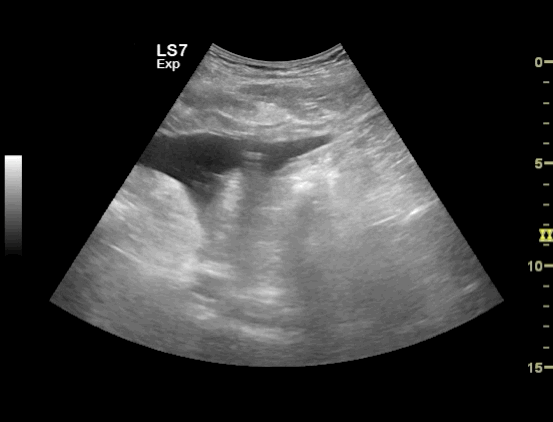

The video clip shows a small rim of free fluid along the liver edge with extensive free fluid noted amongst the intestinal loops

Free Fluid Around the Intestinal loops

Free Fluid in between the Intestinal loops